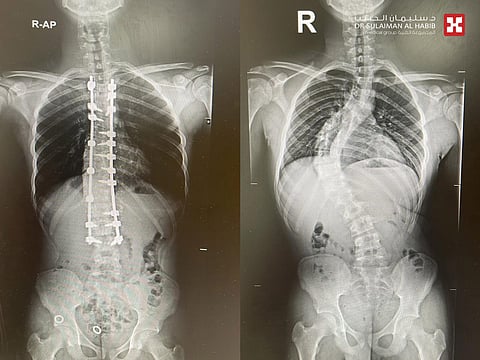

مفيداً بأنه تم إخضاعه لمجموعة من الفحوصات بالأشعة السينية الرقمية (Digital X-Rays) والتحاليل المخبرية، والتي كشفت عن وجود نسبة اعوجاج تزيد عن 75 درجة في الفقرات الصدرية والقطنية وعدم القدرة على النوم بأريحية، وعقب انتهاء الفريق الطبي من دراسة كافة معطيات النتائج، اتخذوا القرار بالتدخل الجراحي، ووضع حد لمعاناة الشاب، وقد أخضع لعملية جراحية معقدة تحت التخدير العام، تم فيها الإستعانة بجهاز مراقبة الأعصاب أثناء الجراحة "Nerve Conduction Monitoring and Somatosensory Evoked Potential"، بالإضافة إلى جهاز الملاحة العصبية، الأمر الذي ساهم في إنجاح العملية، حيث أجري له تعديل وترميم وتثبيت لفقرات العمود الفقري بنجاح تام، ونقل بعدها للتنويم.

وقال د. الغديّر أن جهود الفريق الطبي تكللت بالنجاح التام ولله الحمد، وقد أبانت نتائج المؤشرات الحيوية تحسن حالته الصحية منذ الساعات الأولى للجراحة، واستطاع الوقوف والمشي بمساعدة أخصائي العلاج الطبيعي، وقد تلقى رعاية طبية فائقة على مدار 3 أيام، خرج بعدها من المستشفى وهو بصحة جيدة، ، كما تم متابعته في العيادة، وتبين تحسن حالته وعودته لممارسة حياته بصورة طبيعية.